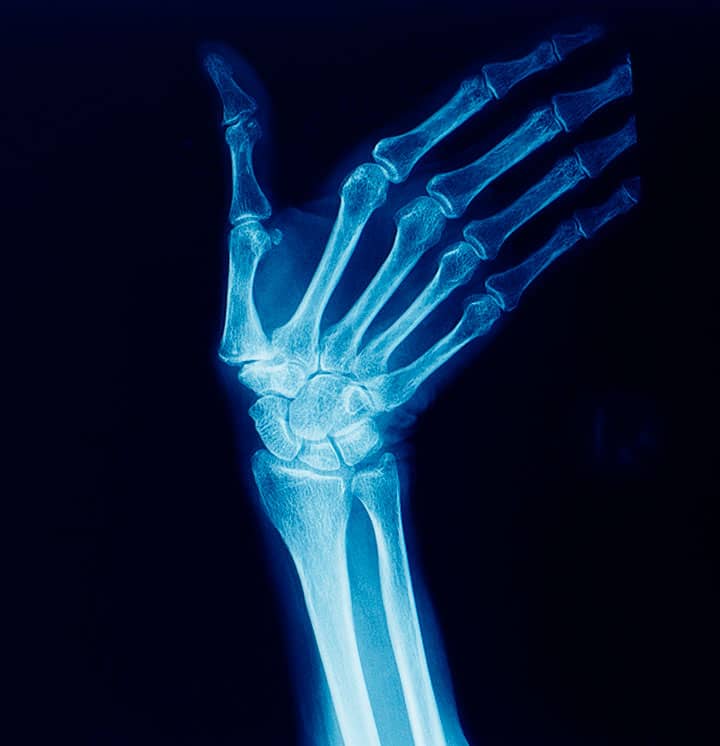

Mão – incidência PA – rotina básica

Justificativa para realização do exame

incidência realizada para o estudo de fraturas, luxações, subluxações corpos estranhos e todas as articulações da mão e patologias, tais como: artrose, artrite, osteomielite e osteoporose.

Principais estruturas demonstradas

toda mão e o punho (carpo) em PA e região distal de antebraço, cerca de 2,5cm. O PA de mão mostra uma visão obliquada do polegar.

Fatores técnicos e posicionamento:

DFF: 1m.

Tamanho do filme/receptor de imagem e sentido: 18x24cm ou 24x30cm no sentido transversal.

Técnica de referência: 3,2mAs e 42KV, fora do bucky.

RC: perpendicular ao receptor de imagem, direcionado para a terceira articulação metacarpofalangeana (MCF).

Posição do paciente e da parte ou região do corpo: colocar o paciente sentado ou em ortostática na extremidade da mesa de exames com a mão pronada e com dedos estendidos.

Mão – incidência oblíqua – rotina básica

incidência realizada para o estudo de fraturas, luxações, subluxações corpos estranhos e todas as articulações da mão e patologias, tais como artrose, artrite, osteomielite e osteoporose.

toda mão e o punho (carpo) obliquados e região distal de antebraço, cerca de 2,5cm.

Posição do paciente e da parte ou região do corpo: colocar o paciente sentado ou em ortostática na extremidade da mesa de exames com a mão obliquada.